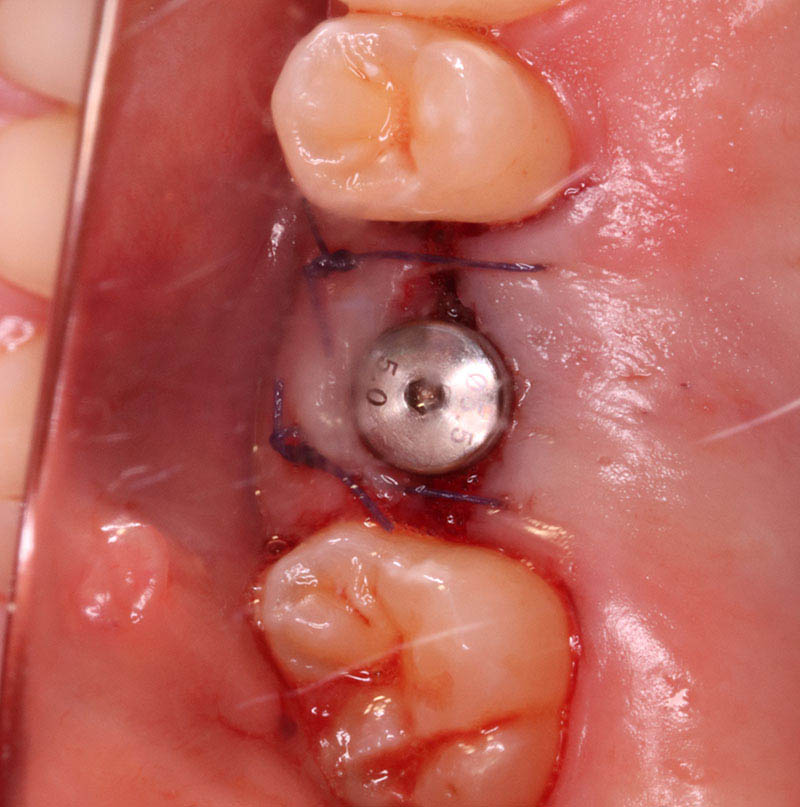

インプラント埋入手術

インプラントの埋入に関しては1回法で行いました。抜歯した部位の骨はしっかりと治癒していました。インプラント埋入後はヒーリングキャップを装着しました。手術時は特に大きな問題はなく無事に手術が終了しました。インプラントの露出を避けるためにも骨幅が少しでも広いところに埋入するために理想的な位置よりは少し後ろになっています。